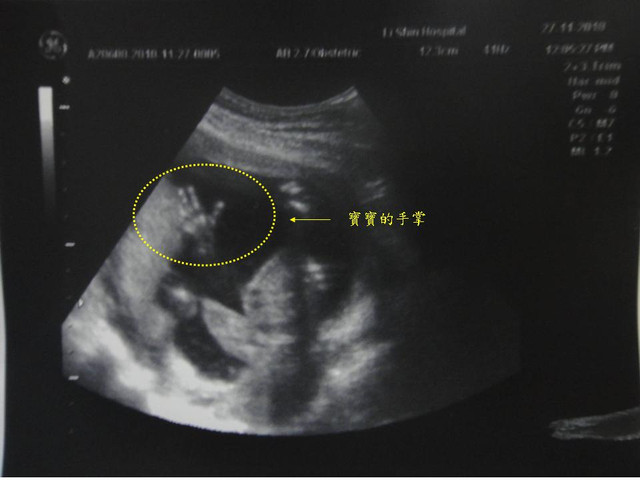

當天,我家小荳荳很配合醫生叔叔進行檢查,

重要時刻開獎囉!呵!我們是美美的小公主,讚唷!